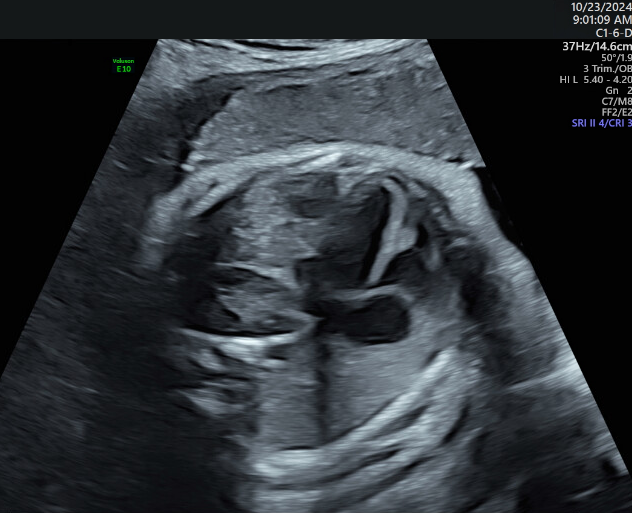

Patient was referred to MFM office for intrauterine growth restriction and incomplete anatomy views from her primary OB office. Upon ultrasound examination, an absent left kidney was quickly suspected, then later located superior to the stomach. Two weeks later, the patient returned for an amniocentesis and Dopplers.

Patient was sent for an MRI due to a possible ectopic kidney or congenital diaphragmatic hernia based on ultrasound exam. The MRI confirmed a posterior congenital diaphragmatic hernia containing the left kidney, adrenal, and bowel.